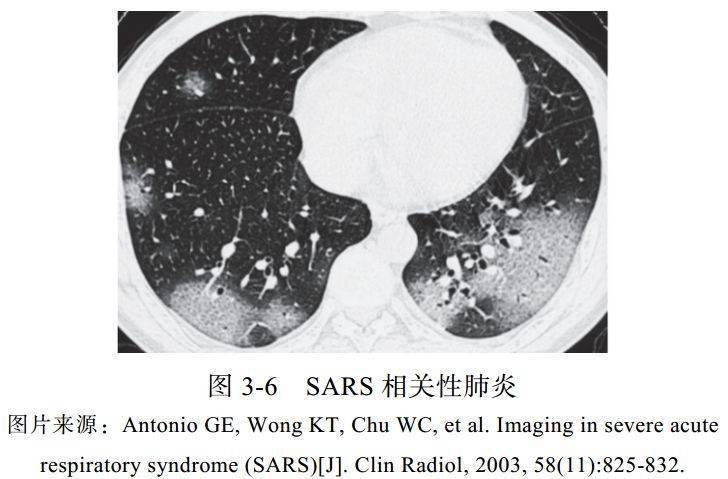

(六)严重急性呼吸综合征

2003 年,严重急性呼吸综合征(SARS)冠状病毒引起的肺炎全球暴发,宿主主要来源于果子狸,潜伏期为 2~10 天,表现为类流感症状,如呼吸难,复发或持续的发热。SARS 冠状病毒通过累及血管紧张素转换酶诱导直接肺损伤,导致弥漫性肺泡损伤。其病死率较高,约 21%的患者为医护人员

影像学表现:

(1)以下肺、单发为主,主要表现为相对清楚的 GGO,其内小血管增多、增粗(图 3-6)

(2)进展迅速,合并实变影

(3)后期出现网状结构影及肺间质纤维化

(4)空洞、淋巴结肿大及胸腔积液不是常见的表现